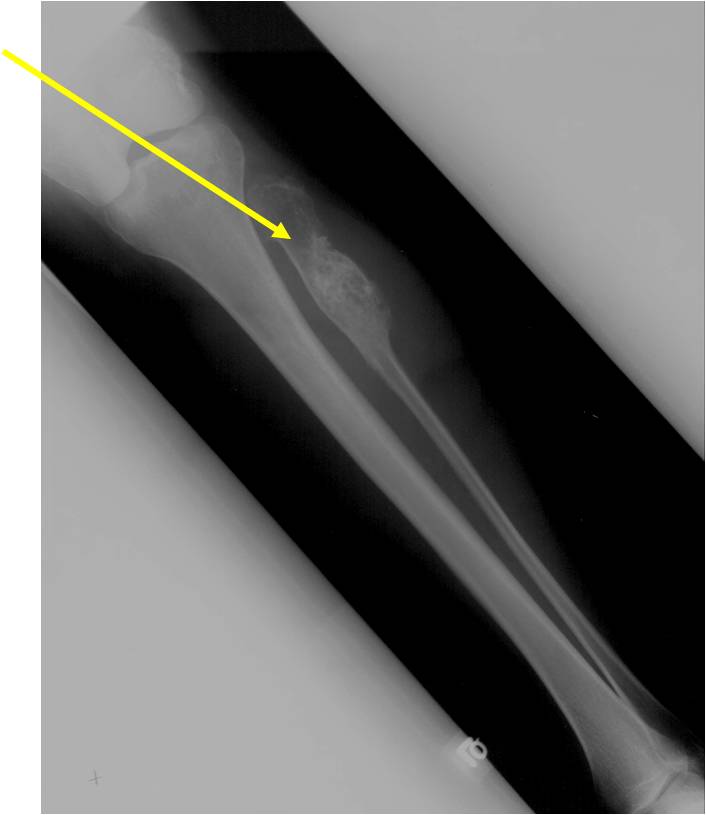

- Localized, radiolucent defect usually with punctate calcifications

- Calcifications are stippled, punctate, popcorn like calcifications and “Ring and Arc” calcifications

- Grows eccentrically or concentrically (phalanges)

- Cortex may be scalloped and thinned in the phalanges

- Geographic lytic lesion

- Expansile remodeling with thinned cortex

- Chondroid matrix with calcifications in majority of tumors

- Digits: Impending or actual pathological fracture

- Intralesional curettage and bone graft or cement